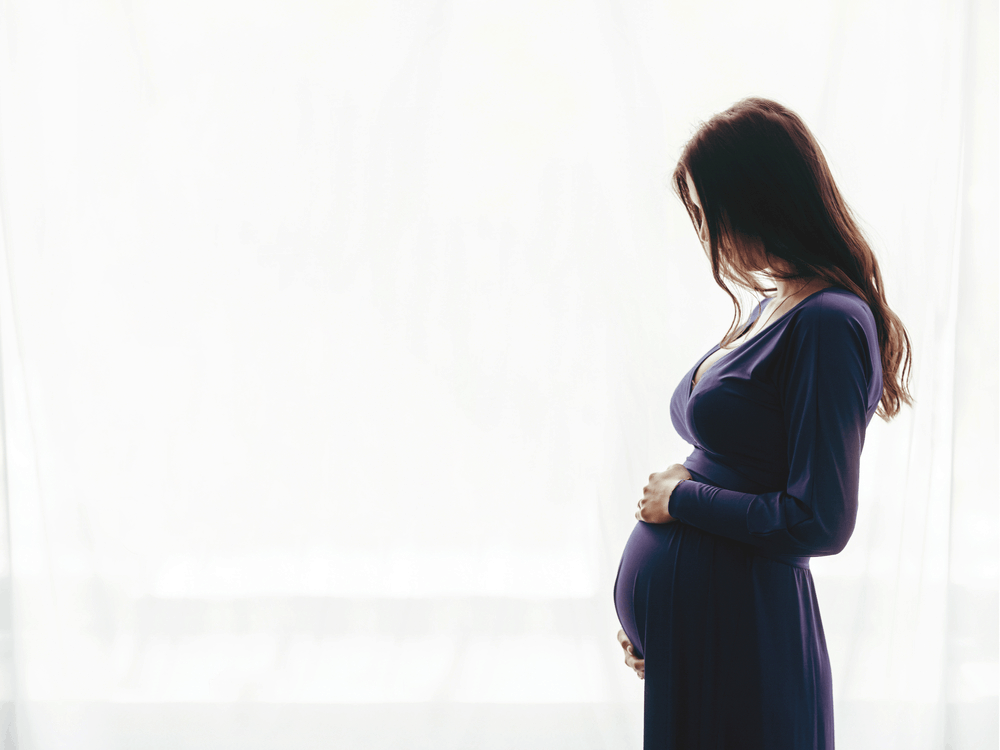

ကိုယ်ဝန်ဆောင်မေမေ သန်ချလို့ရလား

ကိုယ်ဝန်ဆောင်ချိန်မှာ မေမေရော ဗိုက်ထဲက ဘေဘီလေးပါ ကျန်းမာစေဖို့အတွက် အနေအထိုင် အစားအသောက် အစစအရာရာကို ဂရုစိုက် ရပါတယ်။ အစားအသောက်ကိုတောင် ဂရုစိုက်နေရချိန်မှာ ဆေးသောက်ဖို့ဆိုရင် ပိုပြီးတောင် ဂရုစိုက်ရမှာပါ။ ဒီလို အစစအရာရာ ဂရုစိုက်နေရချိန်မှာ သိချင်နေလောက်မယ့် မေးခွန်းလေးတစ်ခု အကြောင်း ပြောပြပေးချင်ပါတယ်။ ဒါကတော့ ကိုယ်ဝန်ဆောင်မေမေ သန်ချလို့ရလား ဆိုတာပါ။ ကိုယ်ဝန်ဆောင်ချိန်မှာ သန်ချလို့ရလား ဆိုတာကို မပြောခင် သန်ချတာနဲ့ ပတ်သက်တဲ့ အကြောင်းလေး ပြောပြပေးချင်ပါတယ်။ ဘာတွေကများ ကိုယ်ဝန်ဆောင် မေမေတွေကို သန်ထစေတာလဲ ကိုယ်ဝန်ဆောင် မေမေတွေကို သန်ထစေတဲ့ အကြောင်းအရင်းတွေကတော့ သေချာ ကျက်အောင် မချက်ထားတဲ့ ငါးတွေကို စားတာ သေချာ ကျက်အောင် ချက်မထားတဲ့ ဝက်သားစားတာ သေချာ ချက်မထားတဲ့ အမဲသား စားမိတာ လူတွေဆီကနေ အချင်းချင်း ကူးစက်ခံရတာ […]